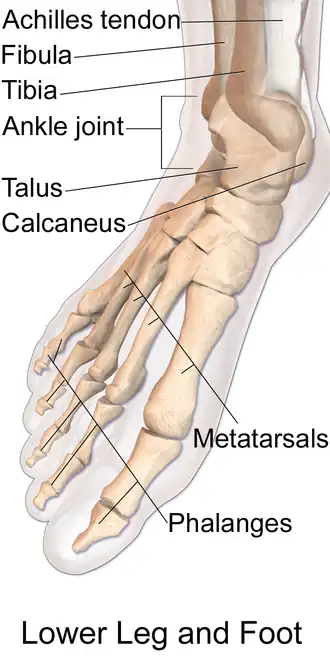

Anatomy of the right foot | |

The talus (/ˈteɪləs/; Latin for ankle[1] or ankle bone;[2] pl.: tali), talus bone, astragalus (/əˈstræɡələs/), or ankle bone is one of the group of foot bones known as the tarsus. The tarsus forms the lower part of the ankle joint. It transmits the entire weight of the body from the lower legs to the foot.[3]

The talus has joints with the two bones of the lower leg, the tibia and thinner fibula. These leg bones have two prominences (the lateral and medial malleoli) that articulate with the talus. At the foot end, within the tarsus, the talus articulates with the calcaneus (heel bone) below, and with the curved navicular bone in front; together, these foot articulations form the ball-and-socket-shaped talocalcaneonavicular joint.

The talus bone of the ankle joint connects the leg to the foot.